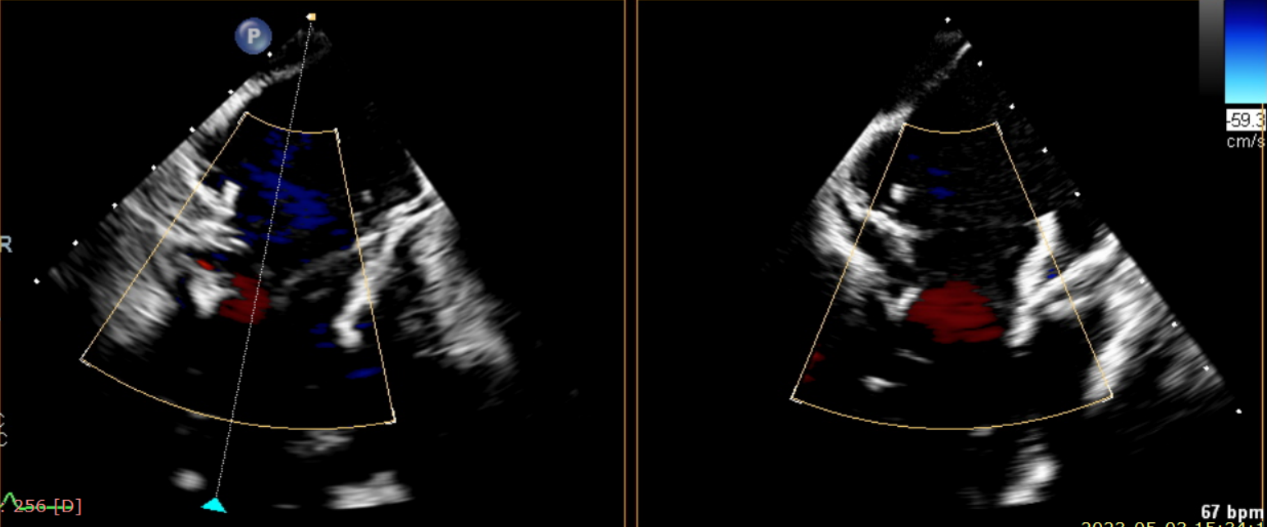

術(shù)后超聲提示僅殘余輕微瓣周漏